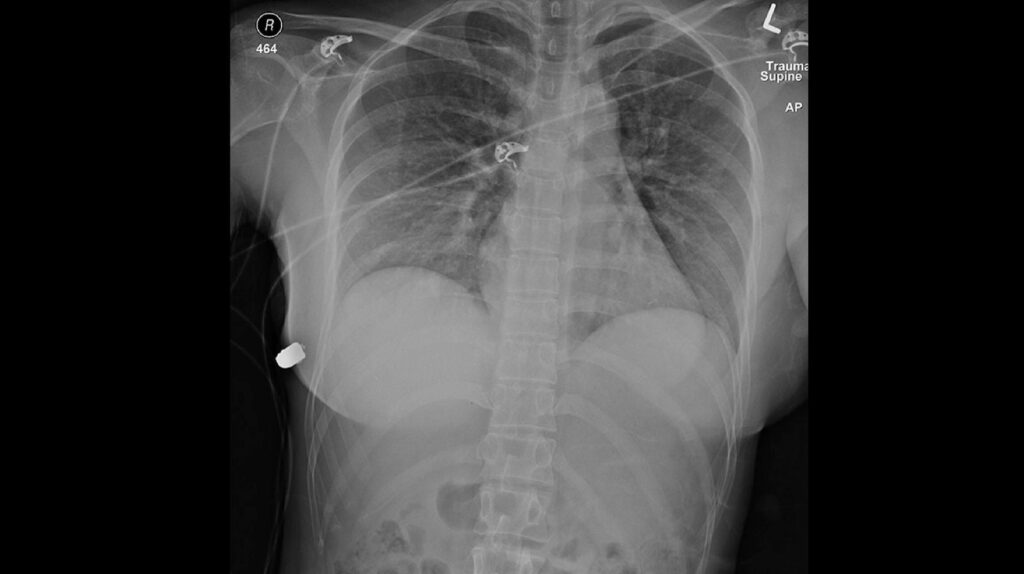

Los implantes de silicona de una mujer desviaron una bala que podría haber sido letal, evitando que llegara a su corazón, según los médicos. Sorprendentemente, esta no es la primera vez que un caso así aparece en la literatura médica. La milagrosa desviación de bala se detalló a principios de mes en un informe médico publicado…